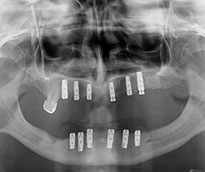

Ýmplant

İmplant (Diş kökü olmayan bölgelere uygulanan suni kökler)